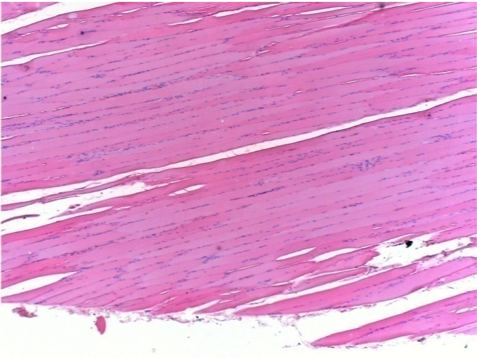

L:Pretibial-No treatment

R:Pretibial-After 0.1 ml NaCl 0.9% IM

L : Control-100xD10